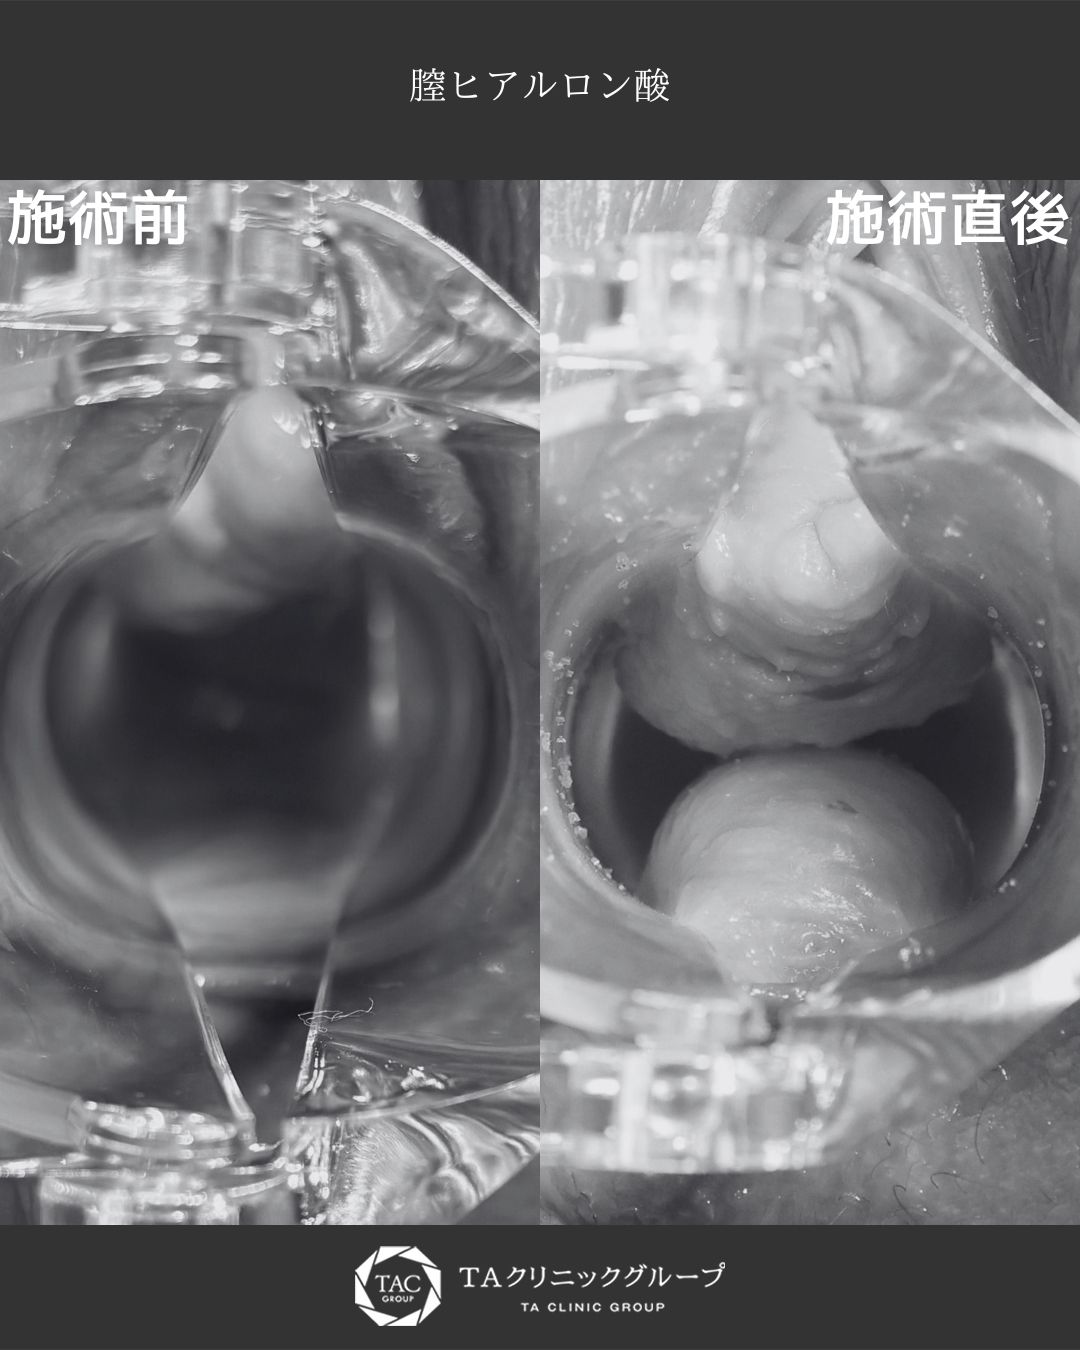

出産後・加齢による膣のゆるみに|膣ヒアルロン酸注入症例|女性器エイジング治療の症例

膣ハイフ(ヴィーナスハイフ)で膣圧向上/膣縮小術

山田 真里江 医師 担当: 山田 真里江 医師